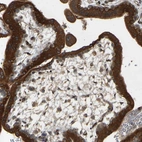

Immunohistochemical staining of human placenta shows strong cytoplasmic positivity in trophoblastic cells.